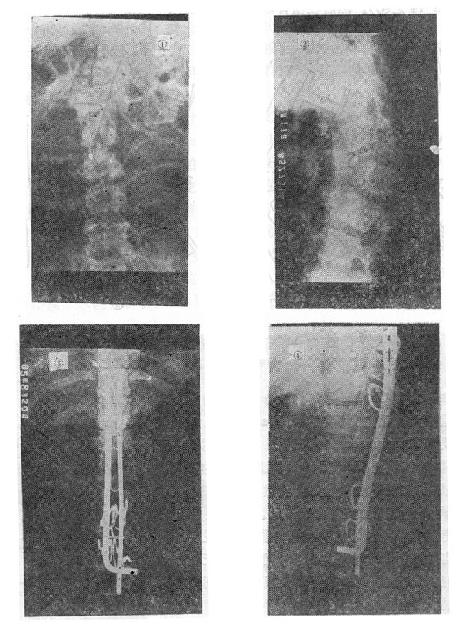

(三)爆裂型骨折的治疗 如不合并严重的神经系统症状,损伤又在两周以内者,可以用双Harrington法,撑开矫正,或用Dick手术;可以获得满意的结果(图73-13)。复位后需融合相邻两个椎间隙,因为CT常显示在爆裂型骨折中,相邻的上、下两个椎间盘均有损伤,如不融合,日后取棍后会出现腰痛。使用本法时,如前纵韧带完整,则很容易恢复椎体前方的高度。但爆裂型骨折存在下述三种情况时,需行前路减压术:①合并神经系统症状较重者;②就诊较晚,已两周以上者(常常10天以上就复位比较困难);③脊柱CT扫描显示已有较大的骨折片突出椎管内,使髓腔管变窄超过30%以上者,预示后纵韧带已有明显损伤,使用后路手术方法已无法使骨折片复位。Kostuik复习了日本和多伦多治疗脊柱骨折的结果后证实,前路减压术能使膀胱、肛门及肢体功能得到更好的恢复。

爆裂型骨折的治疗

图73-13 爆裂型骨折的治疗 ①术前,骨折脱位;②术后,侧位;③术后,正位